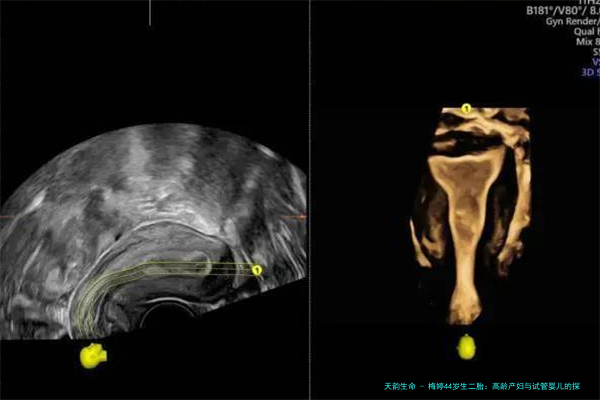

那么,梅婷的二胎是不是试管婴儿呢?目前没有官方消息证实这一点。试管婴儿技术,简单说就是通过体外受精帮助怀孕,近年来在中国越来越普及。数据显示,从2019年到2024年,中国每年进行的试管婴儿周期数从约30万例增加到近50万例,其中高龄女性占比不小。为什么高龄产妇会考虑试管?主要是因为自然受孕几率低,而试管能提高成功率。梅婷44岁生娃,如果自然受孕,几率可能只有5%左右,但通过试管,可以提升到20%-30%。我猜,梅婷可能私下咨询过医生,但出于隐私,她没公开。这让我想起其他明星,比如徐熙媛(大S),她在40多岁生二胎时,就曾透露过使用过辅助生殖技术。不管怎样,选择试管不是什么丢人的事,反而是科技给现代女性的一份礼物。